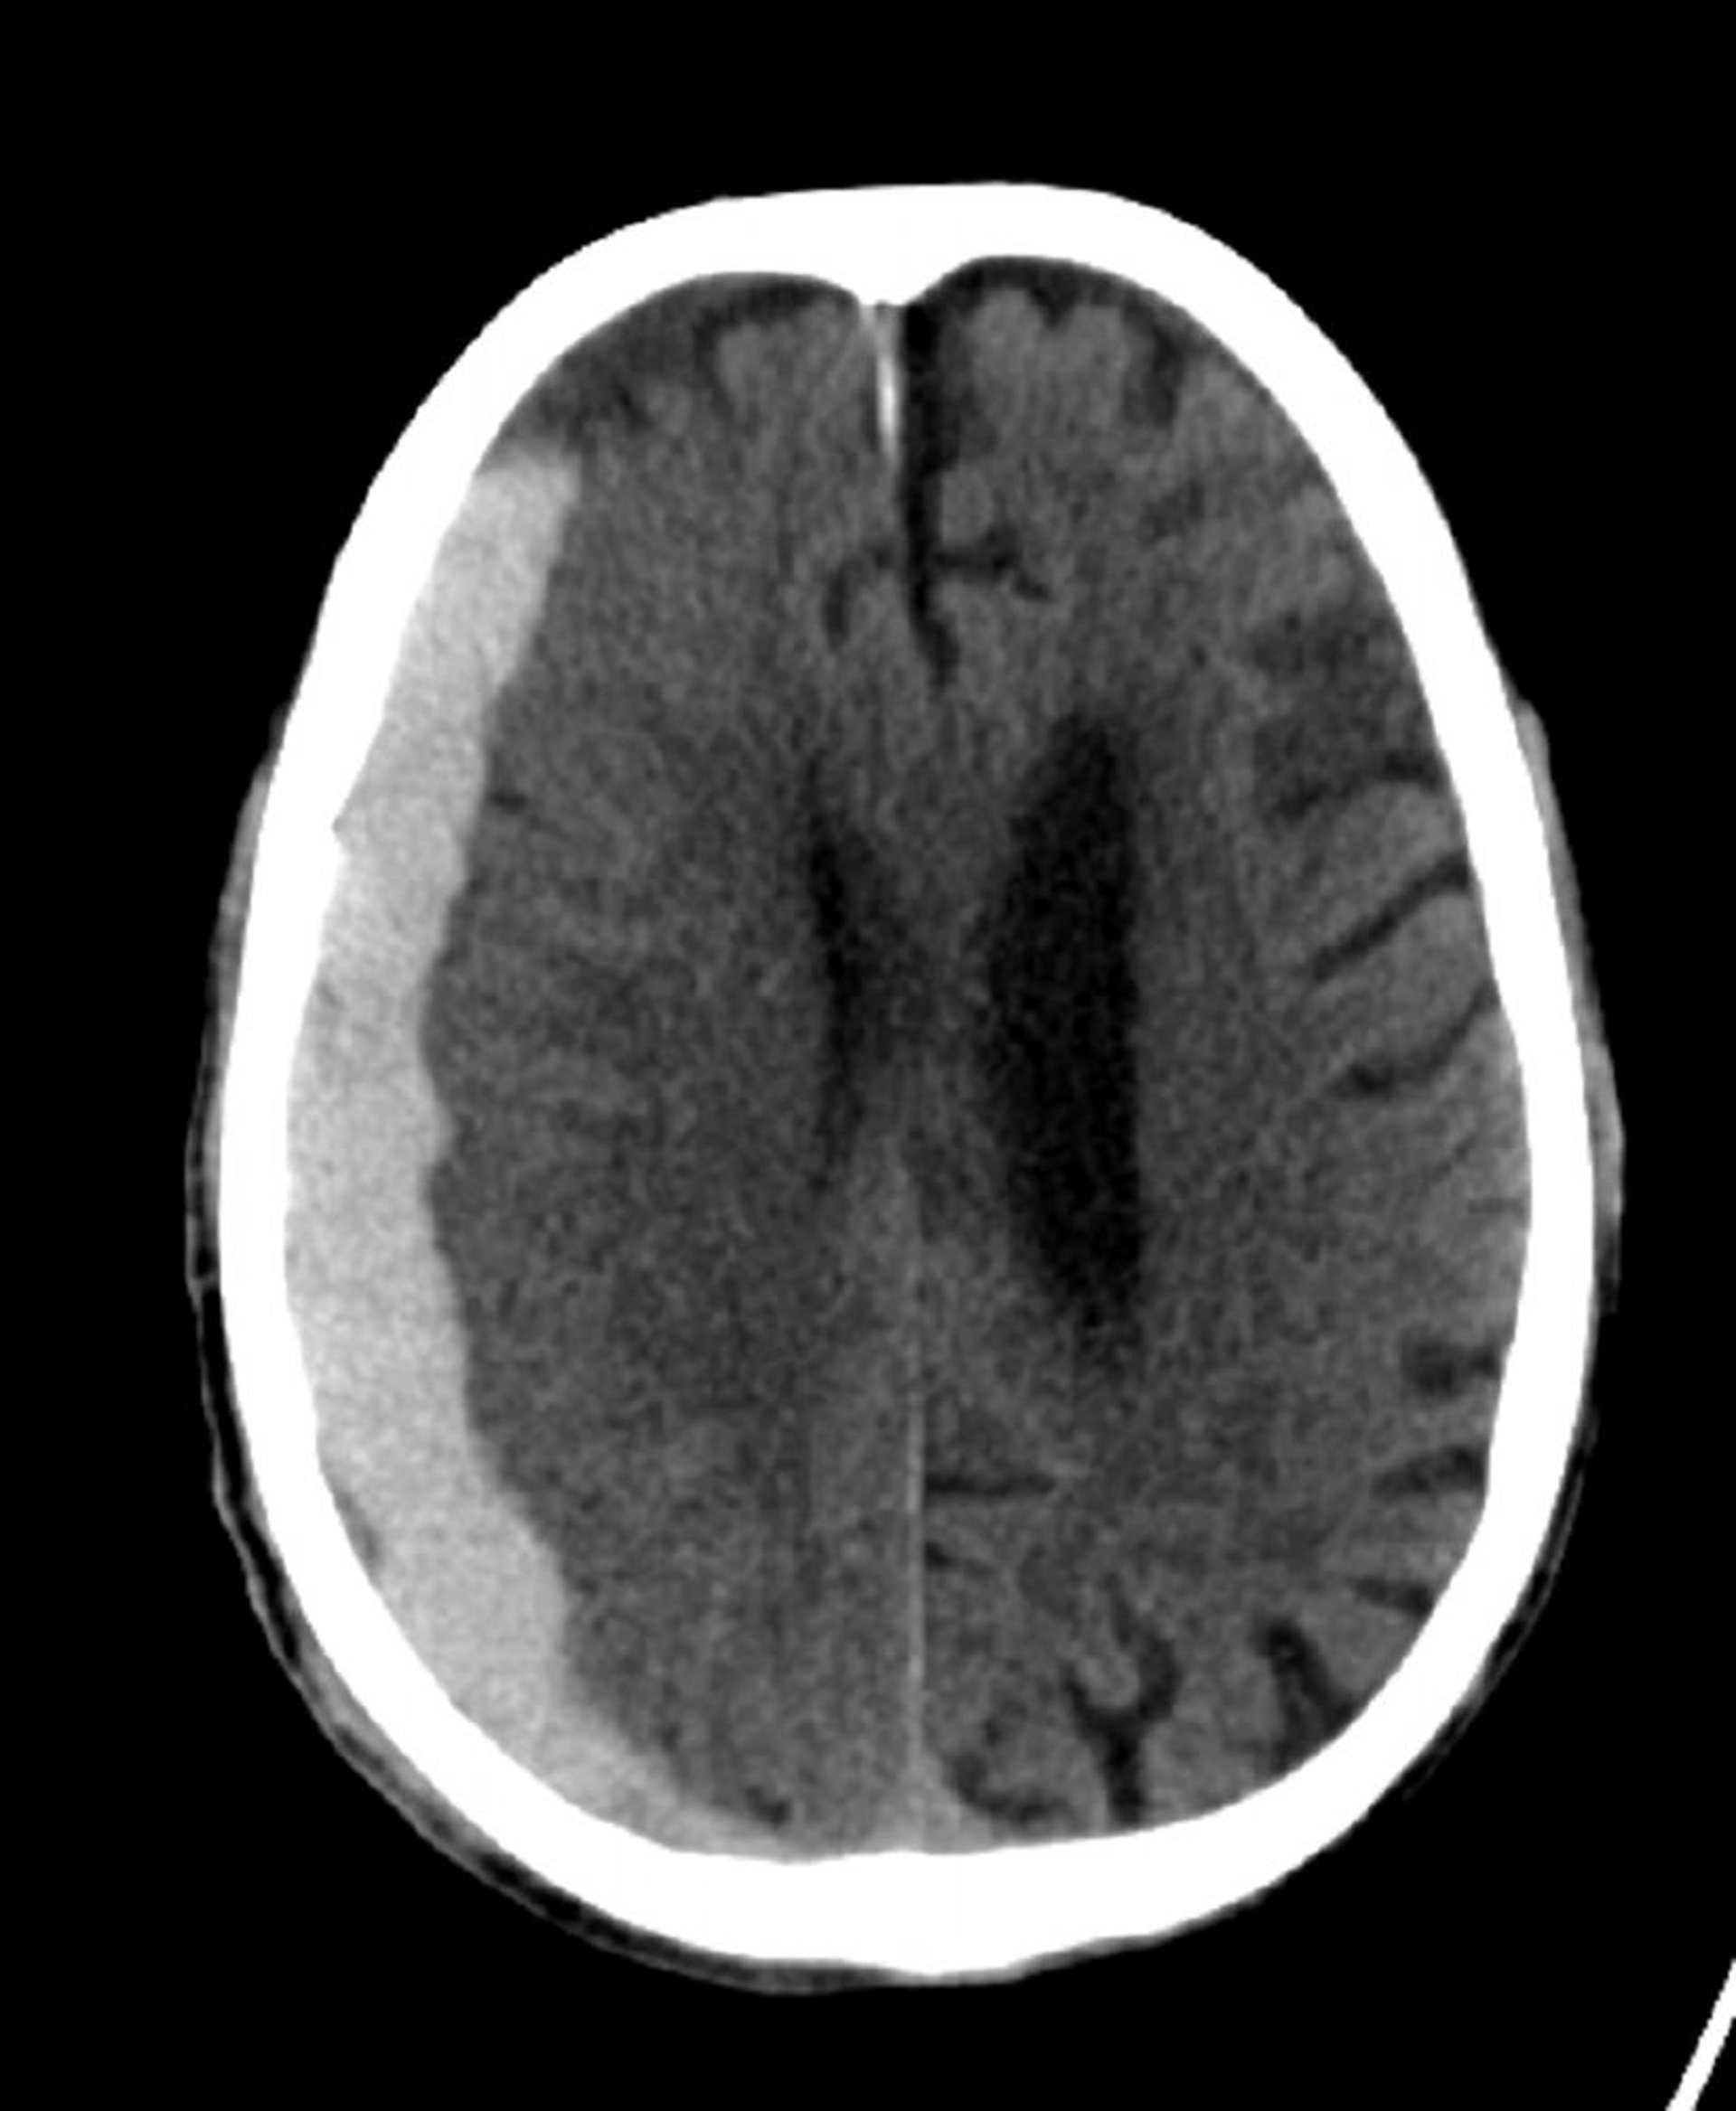

Subduralblutung (CT)

Klassische halbmondförmige Hyperdensität, die sich über die Nahtlinien erstreckt.